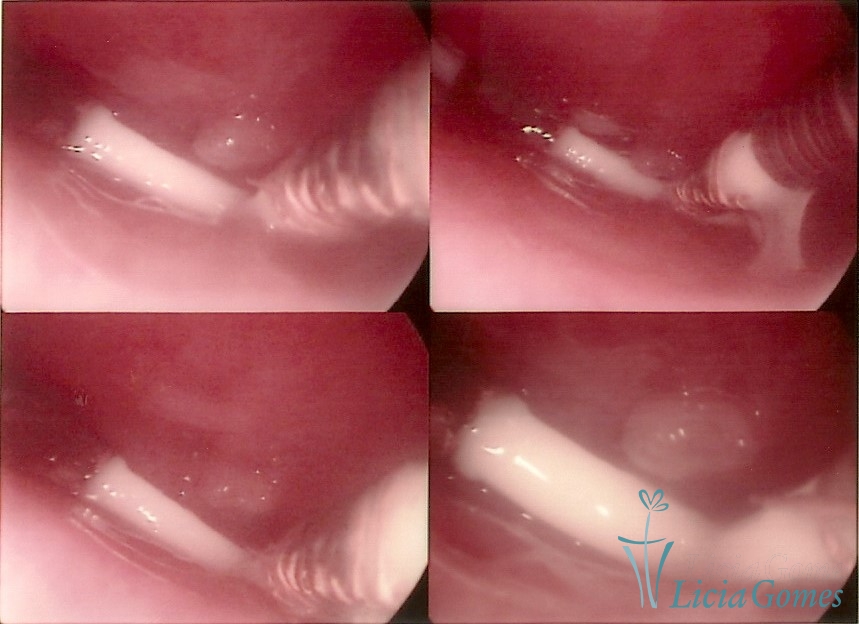

Canal cervical com fio do DIU